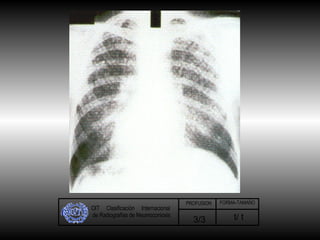

OIT  Clasificación  Internacional de Radiografías de Neumoconiosis t/ t 3/3 PROFUSION FORMA-TAMAÑO